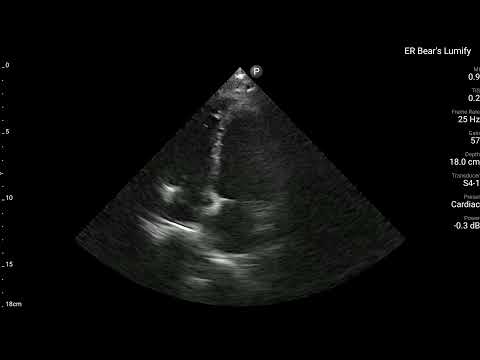

當時我用了自己Lumify做了Echo,大家會希望在哪個地方看出什麼問題呢?

所以我們在ECG看到懷疑是Post.wall MI,當然我們超音波的目光就要放到Post.wall的附近(Segment 4、5、10、11都要看),是否有明顯RWMA。如果有,那麼超音波的發現就和ECG的發現完全吻合,就更可證明這確實就是Post.wall MI。

看Fig.5左側,可以知道A4C其實不容易看到Post.wall。A2C與PSAX可以看到。

- PSAX是看縱切面,可以看到Segment 4、5、10、11

PSAX是最佳可以看到Post.wall與其附近RWMA的最好view。

回頭看看上面的POCUS Clip(PSAX view),把一根手指頭放在LV中間,有沒有發現Segment 4、5附近是不是不太動。

賓果!!!!

POCUS finding is compatible with ECG finding.

Tips:如果懷疑Post.wall MI →PSAX view就最好eyeballing觀看的view